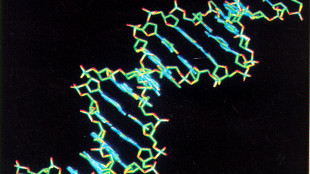

Malattie rare, con studio Telethon arriva diagnosi in bambini dopo 8 anni di attesa

Dato un nome a malattia nel 49% dei casi analizzati, identificati 16 nuovi geni patogeni